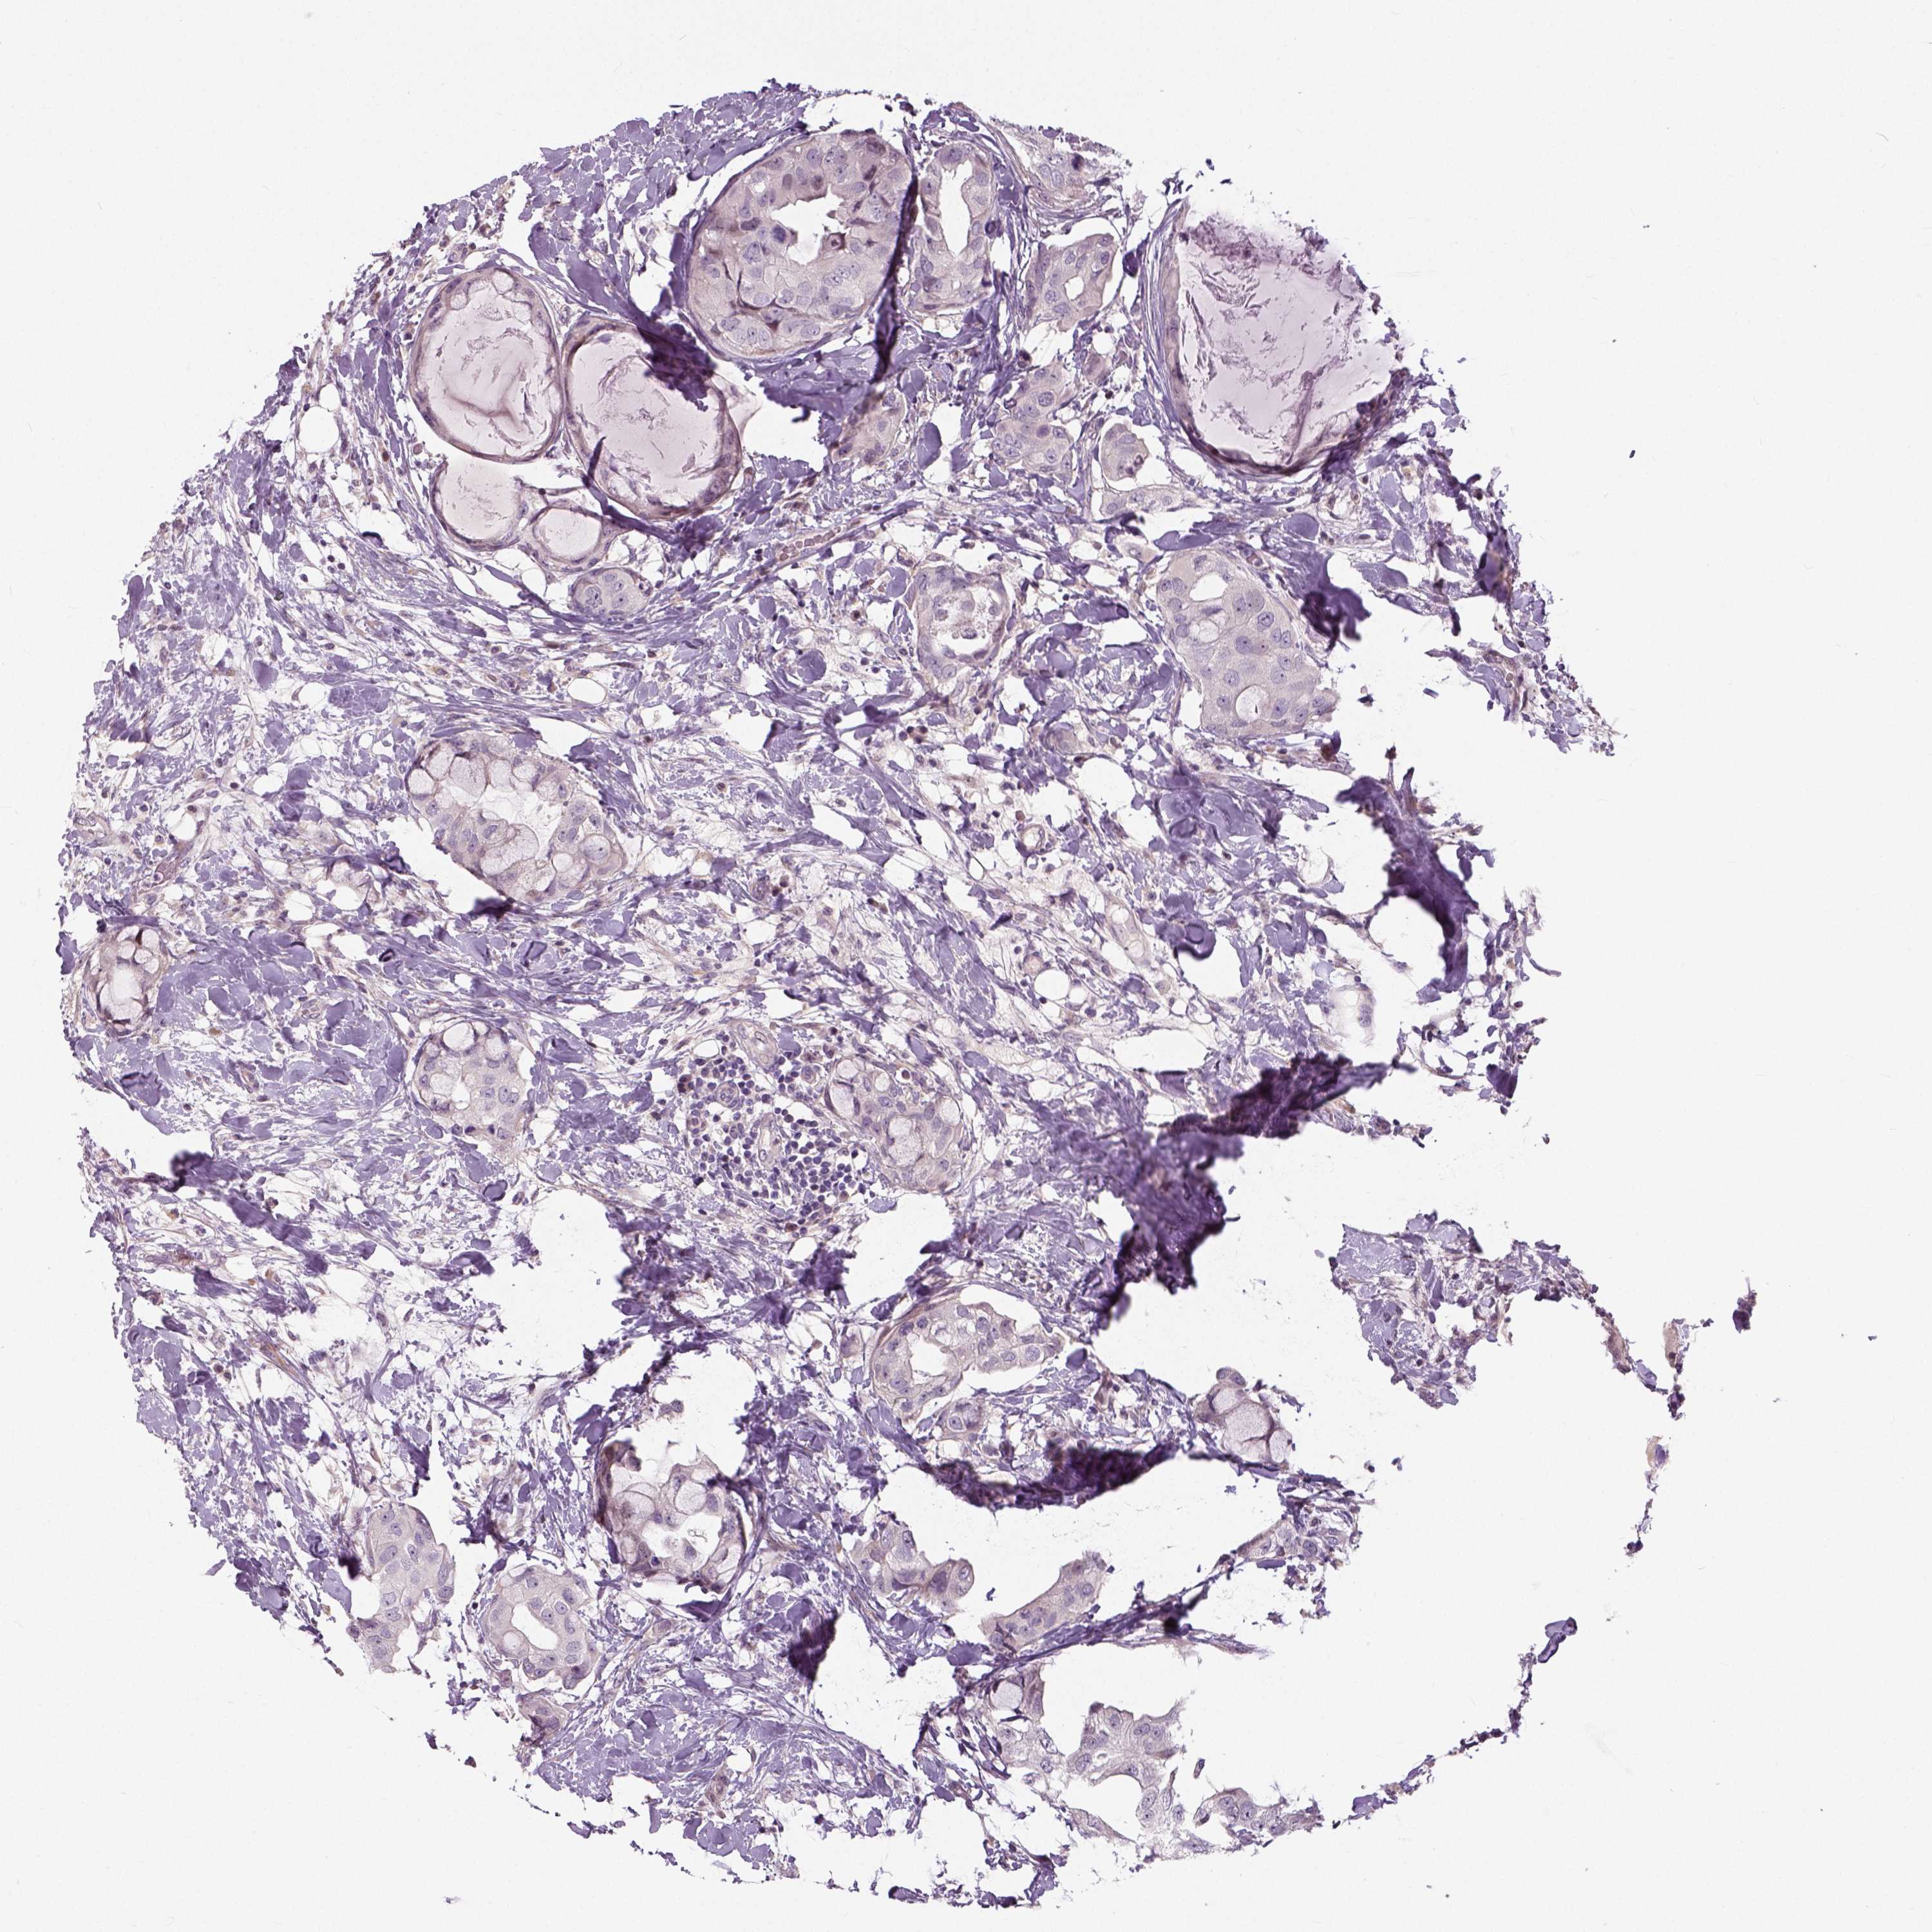

CANCER BREAST CANCER Show tissue menu

Breast cancer

Human cancer